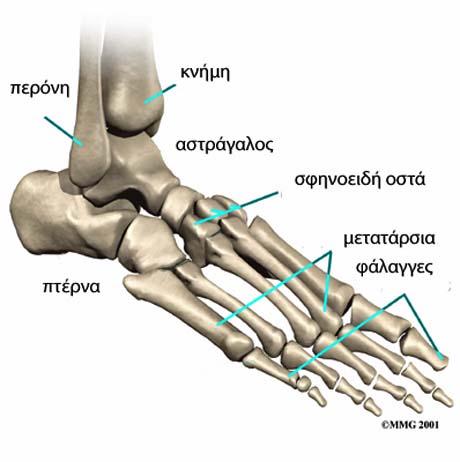

Το πρόσθιο πόδι περιλαμβάνει τα πέντε μακρά οστά που ονομάζονται μετατάρσια καθώς επίσης και τις φάλαγγες που δημιουργούν τα δάκτυλα.

Το πρώτο μετατάρσιο του οποίου η προέκταση οδηγεί στο μεγάλο δάκτυλο του ποδιού, είναι το βραχύτερο και το παχύτερο σε σύγκριση με τα άλλα τέσσερα μετατάρσια και παίζει σημαντικό ρόλο για την επιτέλεση της βάδισης. Κοντά στη κεφαλή του 1ου μεταταρσίου και στη πελματιαία επιφάνειά του βρίσκονται τα σησαμοειδή οστά τα οποία είναι μικρές οστικές δομές πάνω στις οποίες περνούν και καταφύονται μύες του ποδιού.

Το 2ο, 3ο και 4ο μετατάρσιο βρίσκονται ανάμεσα στο 1ο και το 5ο είναι σταθερά και προσφύονται σ’ αυτά μικρή τένοντες δίχως να υπόκεινται σε υψηλά φορτία.

Το ενδιάμεσο πόδι περιλαμβάνει πέντε οστά το οποία είναι το σκαφοειδές, το κυβοειδές και τα τρία σφηνοειδή οστά. Τα οστά αυτά προς τα εμπρός ενώνονται με τις βάσεις των μεταταρσίων και προς τα πίσω με τον αστράγαλο και τη πτέρνα.

Ο οπίσθιο πόδι σχηματίζεται από δύο μεγάλα οστά την πτέρνα και τον αστράγαλο. Ο αστράγαλος συνδέεται με την κνήμη και τη περόνη σχηματίζοντας τη ποδοκνημική άρθρωση ενώ στον αστράγαλο καταλήγει ο Αχίλλειος τένοντας.

Τα οστά του ποδιού.